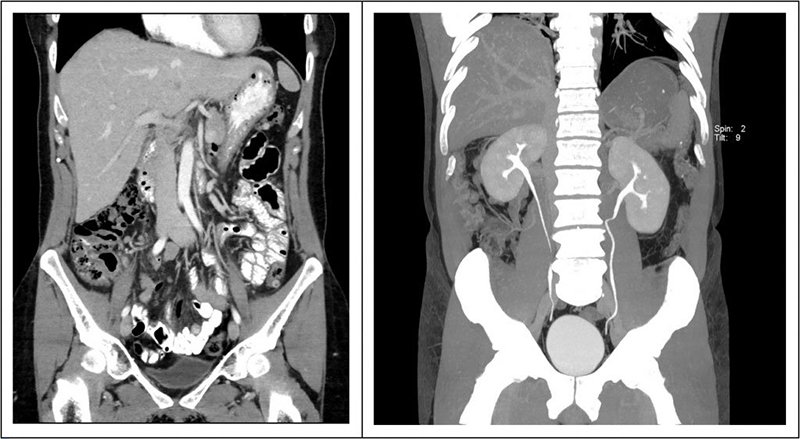

Phương pháp chụp CT ổ bụng còn có tên gọi khác là chụp cắt lớp ổ bụng, là phương pháp chụp cắt lớp vi tính. Đây là phương pháp đang ngày càng được sử dụng phổ biến trong y học và khoa học để chẩn đoán bệnh và nghiên cứu khoa học. Nếu như trước đây, phương pháp này chỉ áp dụng đối với việc chụp sọ não thì ngày nay nếu muốn tầm soát và kiểm tra thì có thể thực hiện ở hầu hết đối với các bộ phận trong cơ thể người và cả ổ bụng. Chỉ mất vài phút để chụp CT sử dụng tia X quang đi qua ổ bụng của người bệnh. Khi nhận được kết quả trên máy tính là những hình ảnh 2D hoặc 3D mặt cắt ngang ổ bụng. Phương pháp này giúp các bác sĩ chẩn đoán những bất thường và bệnh lý ở vùng bụng.

Dựa vào hình ảnh kết quả chụp CT ổ bụng giúp bác sĩ có thêm thông tin để chẩn đoán các nguyên nhân gây bệnh lý sau: Giúp bác sĩ có đủ thông tin để xác định nguyên nhân gây đau bụng. Từ kết quả này bác sĩ có thể loại trừ hoặc chẩn đoán bệnh lý ung thư các tạng trong ổ bụng như ung thư đại tràng, ung thư buồng trứng và ung thư biểu mô tế bào gan. Kiểm tra tình trạng chấn thương ổ bụng và mức độ nhiễm trùng và tình trạng của mật, gan, tụy cũng như phát hiện viêm bể thận, sỏi thận…